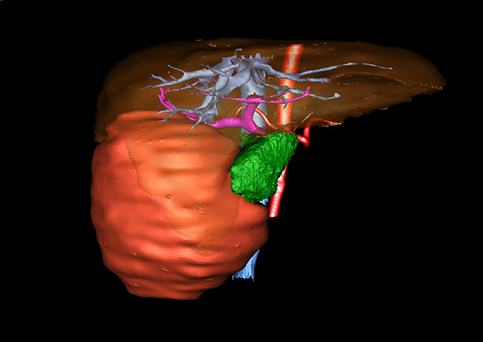

近年来由于数字医学的发展,基于可视化三维重建技术的计算机辅助手术系统极大推进了小儿肝脏肿瘤的精准手术的进步。可以立体透视肝脏解剖、精确掌握肝段的边界、精确测算肝段乃至任意血管所支配的功能体积、准确定位病灶及其与邻近血管的解剖关系,最终对不同手术方案进行比较、筛选和优化。因此,计算机辅助手术规划系统是实现精准肝切除的有力辅助工具,是未来数字外科、精准外科等21世纪外科新理念的重要技术支撑。

计算机辅助手术规划系统具有良好的操作可行性、计算准确性和三维显示效果,可半透明、交互式显示真实的肝内立体解剖关系和空间管道变异,准确计算肝内管道的直径、走行角度,两点间的垂直距离,和任意血管的支配或引流范围等传统二维影像无法获取的信息,有助于实施个体化手术,提高了手术的确定性、预见性和可控性。计算机辅助手术规划系统可直观显示预留肝脏的结构和功能,并可通过虚拟切割功能辅助术者对手术方案进行蹄选和优化,系统评估手术风险和制定对策,改变了部分二维规划的术式和切除范围,使部分二维规划认为不能切除的患者成功手术,提高了手术的根治性、安全性和病变的可切除性,更加符合精准肝脏外科的术前规划要求。详见第11章。

随着计算机技术及影像检查技术的不断发展,以精确的术前影像学和功能评估、精细的手术操作为核心的精准肝切除技术日益受到重视。基于数字医学的计算机辅助手术技术(computer-assisted surgery,CAS)则是实现肝脏精准手术操作的基础。计算机辅助手术系统(CAS)可将术前二维(two dimensional,2D)的CT/MRI影像数据进行三维(three dimensional,3D)重建,建立个体化的肝脏三维解剖模型,清晰显示肝脏内脉管系统的走行及解剖关系,还原病灶与其周围脉管结构的立体解剖构象,准确地对病变进行定位、定性和评估,制定合理、定量的手术方案,实施个体化的肝脏血管取舍分配方案及实施精准肝脏手术。一般认为CAS包括:创建虚拟的患者的图像;患者图像的分析与深度处理;诊断、手术前规划、手术步骤的模拟;术中实时导航。应用本技术后,由于可以更清晰地看出肿瘤的界限,特别是根据肝血管的显影,判断出肿瘤与门静脉及肝静脉的关系以在手术前较准确地估计出手术成功切除的可行性。以往部分根据普通强化CT判断无法手术的病例而被评估为可以成功切除并手术成功。